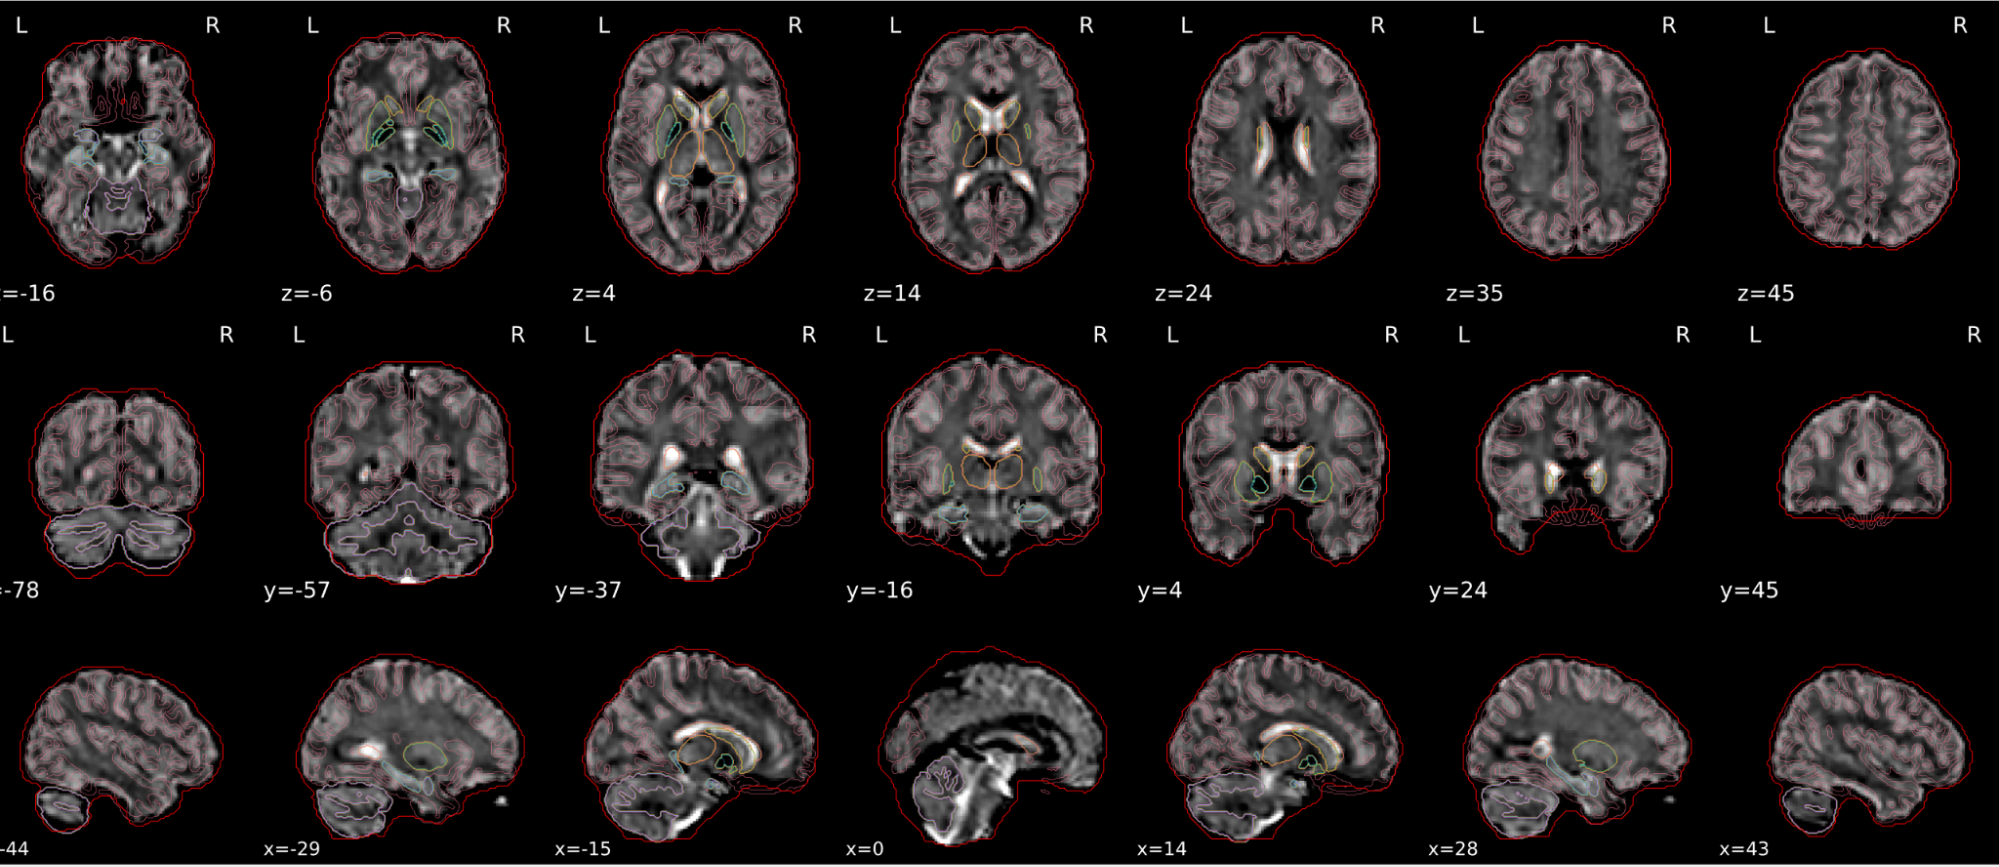

EPI spatial normalisation

This QC step shows the registration of the EPI image to MNI space.

Example of a good subject

- If the registration performed well, you should see an overlap (i.e., correspondence of structures) between the MNI template and the EPI registered to the MNI space.

- If parts of the brain are missing due to the scanner field of view, this is fine. For example, the cerebellum may be cut off for a participant with a large head.

Example of a bad subject

- In case of poor registration, you should see a misalignment of the EPI and the MNI template

Summary

| good | bad |

|---|---|

| Overlap (i.e. match of structures) between the MNI template and the EPI registered in the MNI space | Misalignment of the EPI and the MNI template |

| If parts of the brain are missing because the field of view of the scanner is limited, the EPI spatial normalisation does not have to be excluded e.g. cerebellum cut off in person with large head |

If parts of the brain are missing because the field of view of the scanner is limited, the EPI spatial normalisation does not have to be excluded (e.g. cerebellum cut off in person with large head)